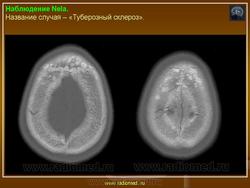

Туберозный склероз

Туберозный склероз (болезнь Бурневилля-Прингла, синдром Бурневилля - Брессау) - глиоз белого вещества мозга, проявляющийся в раннем детстве эпилептическими припадками (в 85%), олигофренией в сочетании с нараста­ющей пирамидной и экстрапирамидной симптоматикой, кожной патологией. В возрасте 4-6 лет на лице в форме бабочки в области носа обычно появляют­ся множественные желто-розовые или коричнево-красные узелки диаметром чуть больше 1 мм - аденомы Прингла, которые обычно признаются аденомами сальных желез, однако есть мнение и о том, что они представляют собой про­исходящую из нервных элементов кожи гамартрому.

Встречаются и аномалии развития извилин мозга в виде микро- и пахигирии. Заболевание чаще носит спорадический характер. Бляшки достигают диаметра 5-20 мм. В коре больших полушарий и мозжечка иногда могут быть обнару­жены пластинчатые тельца, напоминающие амилоид. Происходит дегенерация клеток коры. При КТ-исследовании головы нередко можно выявить кальцифика-ты и глиальные узелки в паравентрикулярной области, субэпендимарно вдоль на­ружных стенок боковых желудочков, в зоне межжелудочкового отверстия Мон­ро, реже - в мозговой паренхиме. На М РТ головного мозга в 60% выявляются гипотеденсивные очаги в одной или обеих затылочных долях, которые расце­ниваются как участки неправильной миелинизации (Козлов А.В., 2002).